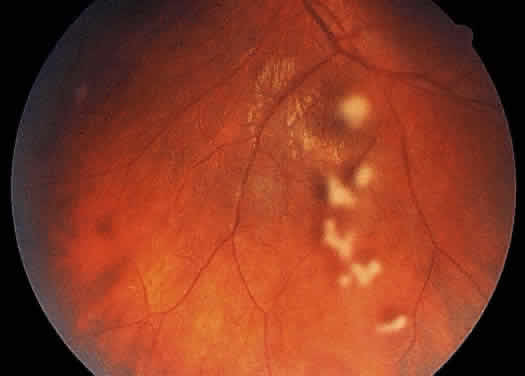

Examination of the posterior segment of the eye must also include an examination of the optic nerve head. Disc edema or hyperemia is frequent in uveitis patients, often preceding the development of macular edema. Neovascularization of the disc is another abnormality that may develop in patients with severe uveitis.36 The optic nerve head may also be a site of granuloma formation (Fig. 12).

Fig. 12. Large optic nerve head granuloma in a patient with sarcoidosis. Note the areas of periphlebitis.

The retinal vessels should be examined for evidence of vasculitis, noting whether the vasculitis affects primarily the veins (phlebitis) or the arteries (arteritis). Patients with sarcoid uveitis commonly have extensive periphlebitis, whereas patients with Behçet's disease may have more of an arteritic picture. Patients with herpetic retinitis may have extensive arteritis and phlebitis, which produce the appearance of “frosted branch angiitis”37 (Fig. 13).

Fig. 13. Fundus photograph of the right eye of a patient with cytomegalovirus retinitis and extensive “frosted branch angiitis.” The active cytomegalovirus retinitis is temporal to the fovea and along the superotemporal arcade.